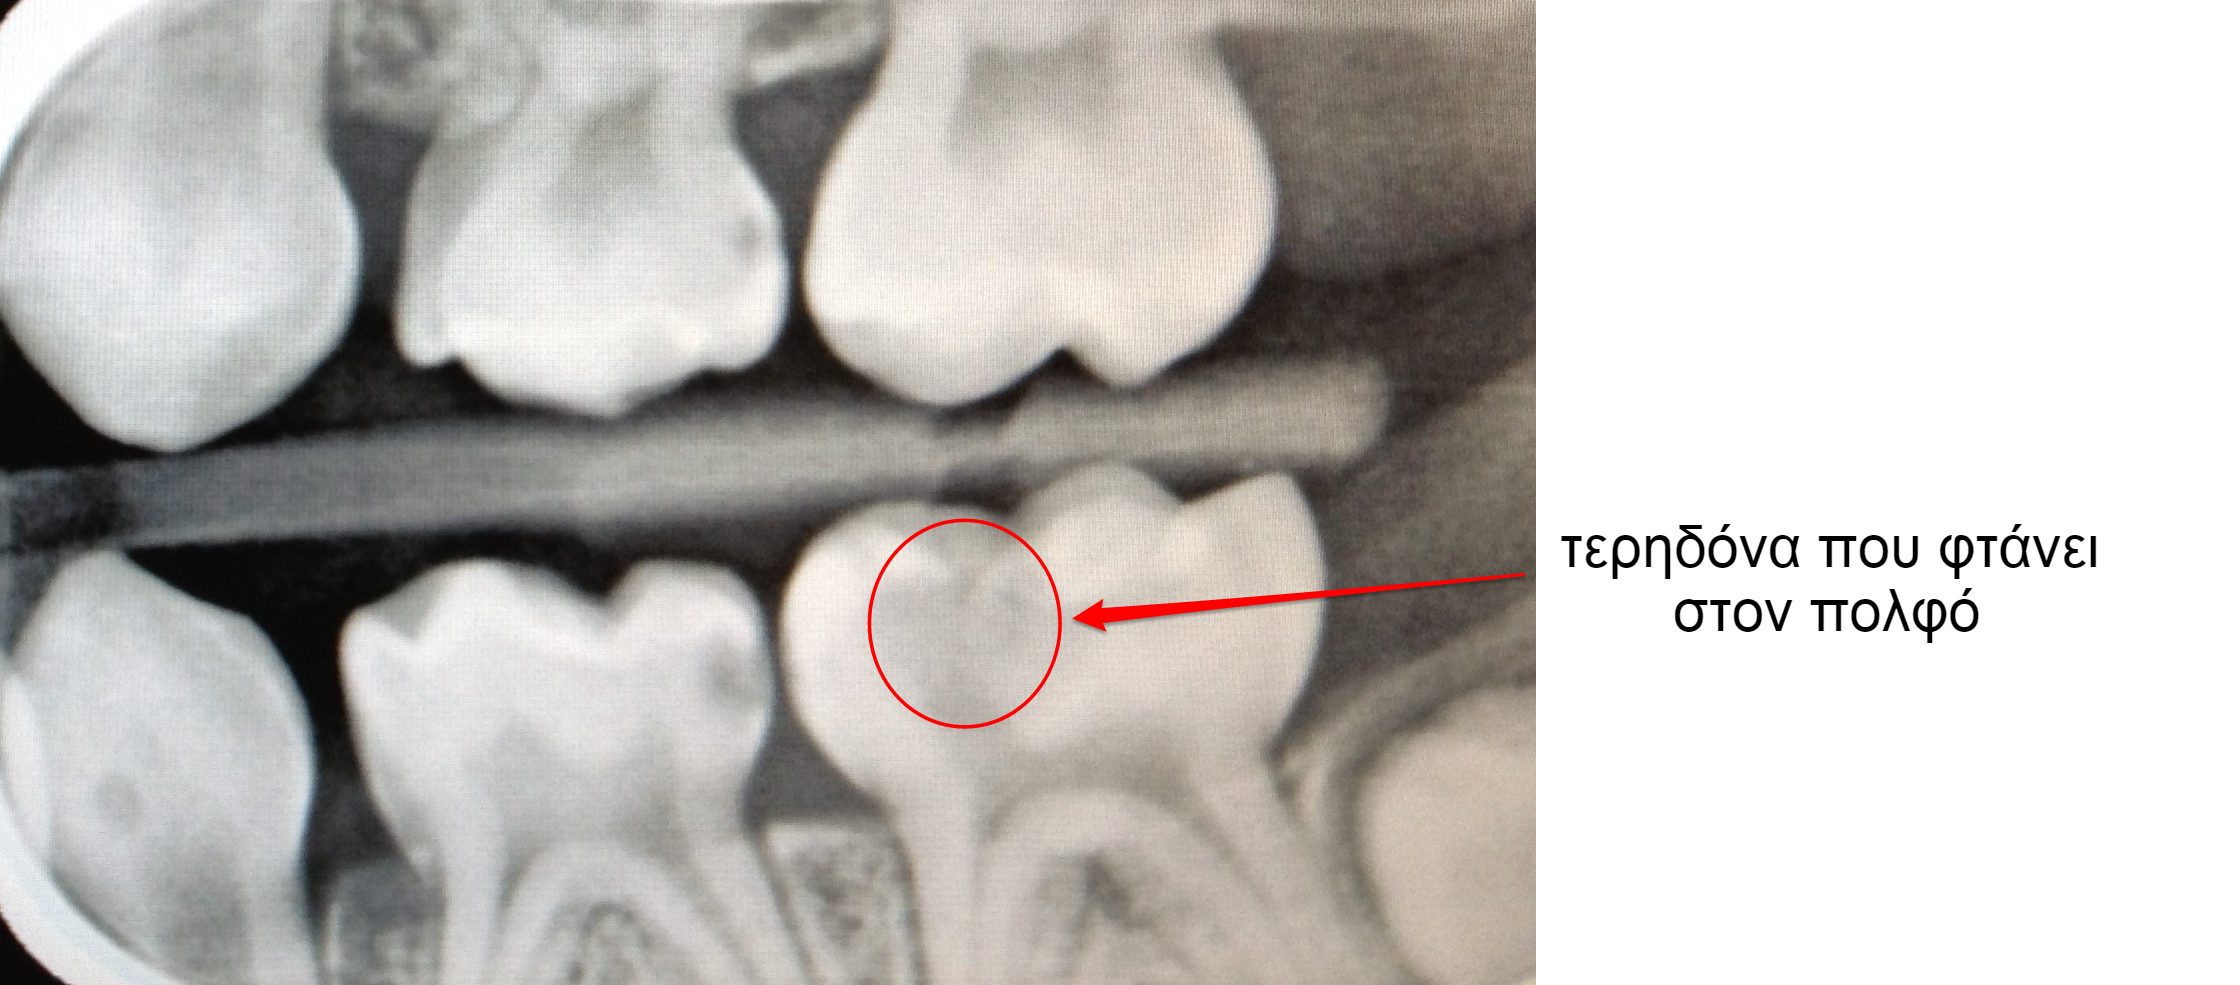

Όταν η τερηδόνα φτάσει πάρα πολύ κοντά στο νεύρο του παιδικού δοντιού, τότε η αντιμετώπιση με σφράγισμα δεν αρκεί διότι ο πολφός (το νεύρο του δοντιού) κινδυνεύει από φλεγμονή και υπάρχει κίνδυνος νέκρωσής του.